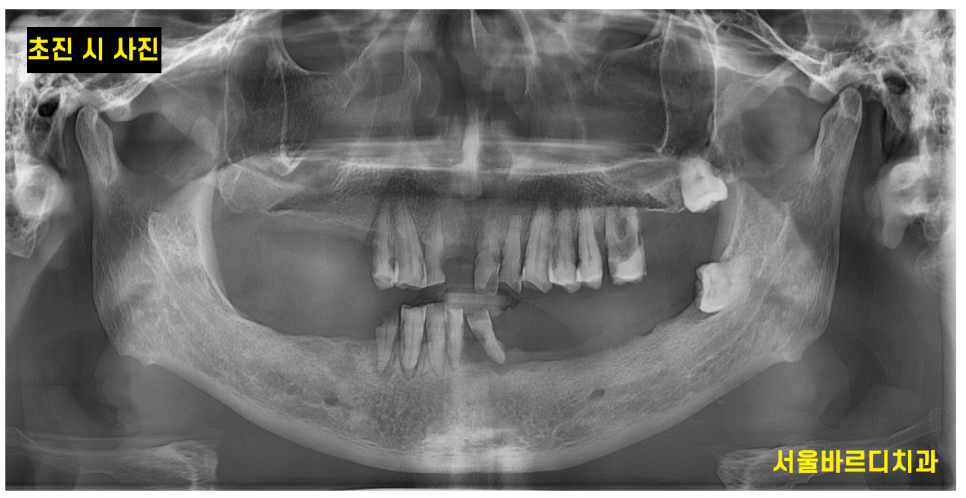

뽑힌 치아도 많았고

앞으로 뽑아야 할 치아도 많았습니다.

상악은 그나마 괜찮았지만

아래 치아 같은 경우 하악 전체 임플란트가 필요했습니다. '

작은 x ray도 찍어보고

ct도 찍어 찍어 최대한 남길 수 있는 치아들은 남기고 싶었으나

아래 치아의 경우 몹시도 흔들리고 충치가 심하여

남아있는 치아 전부 제거가 필요했습니다.